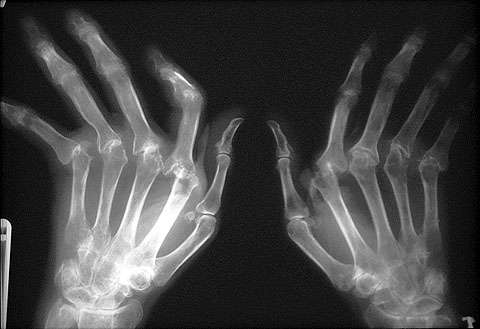

Rheumatoid Arthritis

Ianya

adalah sejenis keradangan arthritis. membran synovial (Synovium)

diserang mengakibatkan keradangan dan kesakitan. Jika tidak dirawat, ia

boleh menyebabkan kecacatan. Rheumatoid Arthritis lebih banyak dihidapi

oleh wanita berbanding lelaki dan kebiasaannya di dalam lingkungan usia

40 hingga 60 tahun. Kanak-kanak dan warga tua juga tidak terkecuali dari

menghidap penyakit ini. Pesakit rheumatoid arthritis mempunyai risiko

darah beku dalam masa 10 tahun pertama selepas didiagnosis.

Gejalanya:

Sendi yang sama sering membengkak, radang, kaku dan sangat menyakitkan.

Jari, lengan, kaki dan pergelangan tangan adalah paling mudah terjejas.

Sendi lembut apabila disentuh. Tangan mungkin merah dan membengkak.

Lebam pada tisu di bawah kulit. Sentiasa berasa letih. Sendi menjadi

lebih kecil. Masalah dan kesakitan beberapa sendi pada masa yang sama.

Ia merebak daripada sendi-sendi yang kecil seperti tangan, pergelangan

tangan, buku lali, kaki, siku, lutut, pinggul, leher, bahu dan rahang.